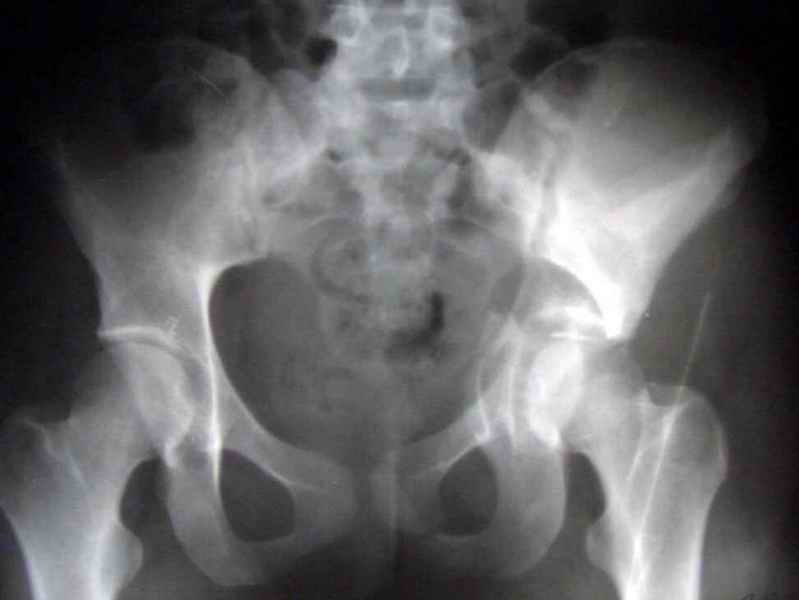

Посылаю схемы и 3D реконструкцию подобного повреждения. Называется он полным высоким двухколонным переломом вертлужной впадины, а "переломы крыла и тела подвздошной кости" входят в это понятие.

Вариантов остеосинтеза много (можно и не оперировть, т.к. конгруентность при таких переломах как правило сохраняется)

1 закрытая репозиция аппаратом + фиксация через проколы винтами

2 закрытая репозиция передней колонны + открытая задней колонны из задне-неружного доступа

3 открытая репозиция передней колонны из подвздошнго доступа + открытая задней колонны из задне-наружного доступа

4 открытая репозиция из илиоингвинального доступа

5 открытая репозиция из Y образного доступа

Я бы ориентировался на Y образный доступ

или из двух если есть сомнения в целостности задних отделов крыла.

прикладываю схему доступа и случай.

Одним задне наружным переднюю колонну не достать, а илио-ингвинальный более сложный не позволяет контролировать суставную поверхность и трудно управлять задней колонной.